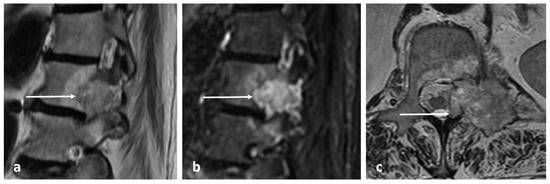

| Giant cell tumour | Mixed cystic and solid expansile lesions, with thin peripheral bony shell. ‘Soap bubble’ appearance. | Secondary ABC change is common, with fluid—fluid levels. Intermediate to low signal intensity on both T1 and T2. Enhancing soft tissue component. |